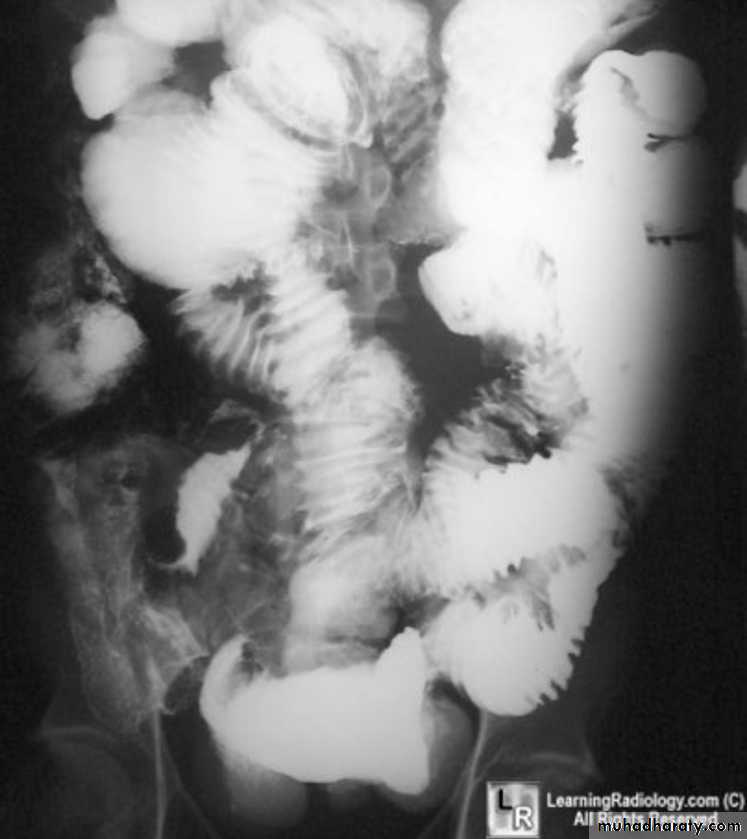

Lymphoma of small bowel

• Splaying & separation of the bowel loops due to enlarged LN• Thickening of the mucosa , irregular in outline ( saw tooth pattern ) .

• LATER stage could be present as sign of Malabsorption syndrome ( flocculation & segmentation of the Ba ) .

Mal absorption syndrome